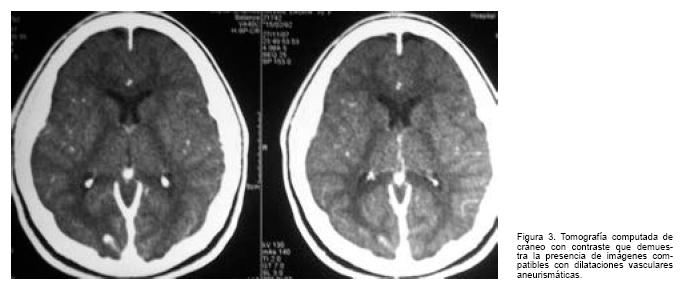

Angiorresonancia magnética de tórax (Figura 2): estenosis focal de la aorta descendente proximal, a nivel del istmo, de 17,7 mm, distal al ostium de la arteria subclavia izquierda. Circulación colateral evidente. HVI.

En los últimos años se han desarrollado otras técnicas de imagen que permiten una valoración más precisa del arco aórtico, destacándose dentro de éstas a la angiorresonancia de tórax (Angio RM Tx.) con inyección de gadolinio. Esta mayor precisión es debida a la reconstrucción tridimensional de las estructuras. La tomografía computada de alta resolución (TCAR) presenta similares resultados.(4,5)